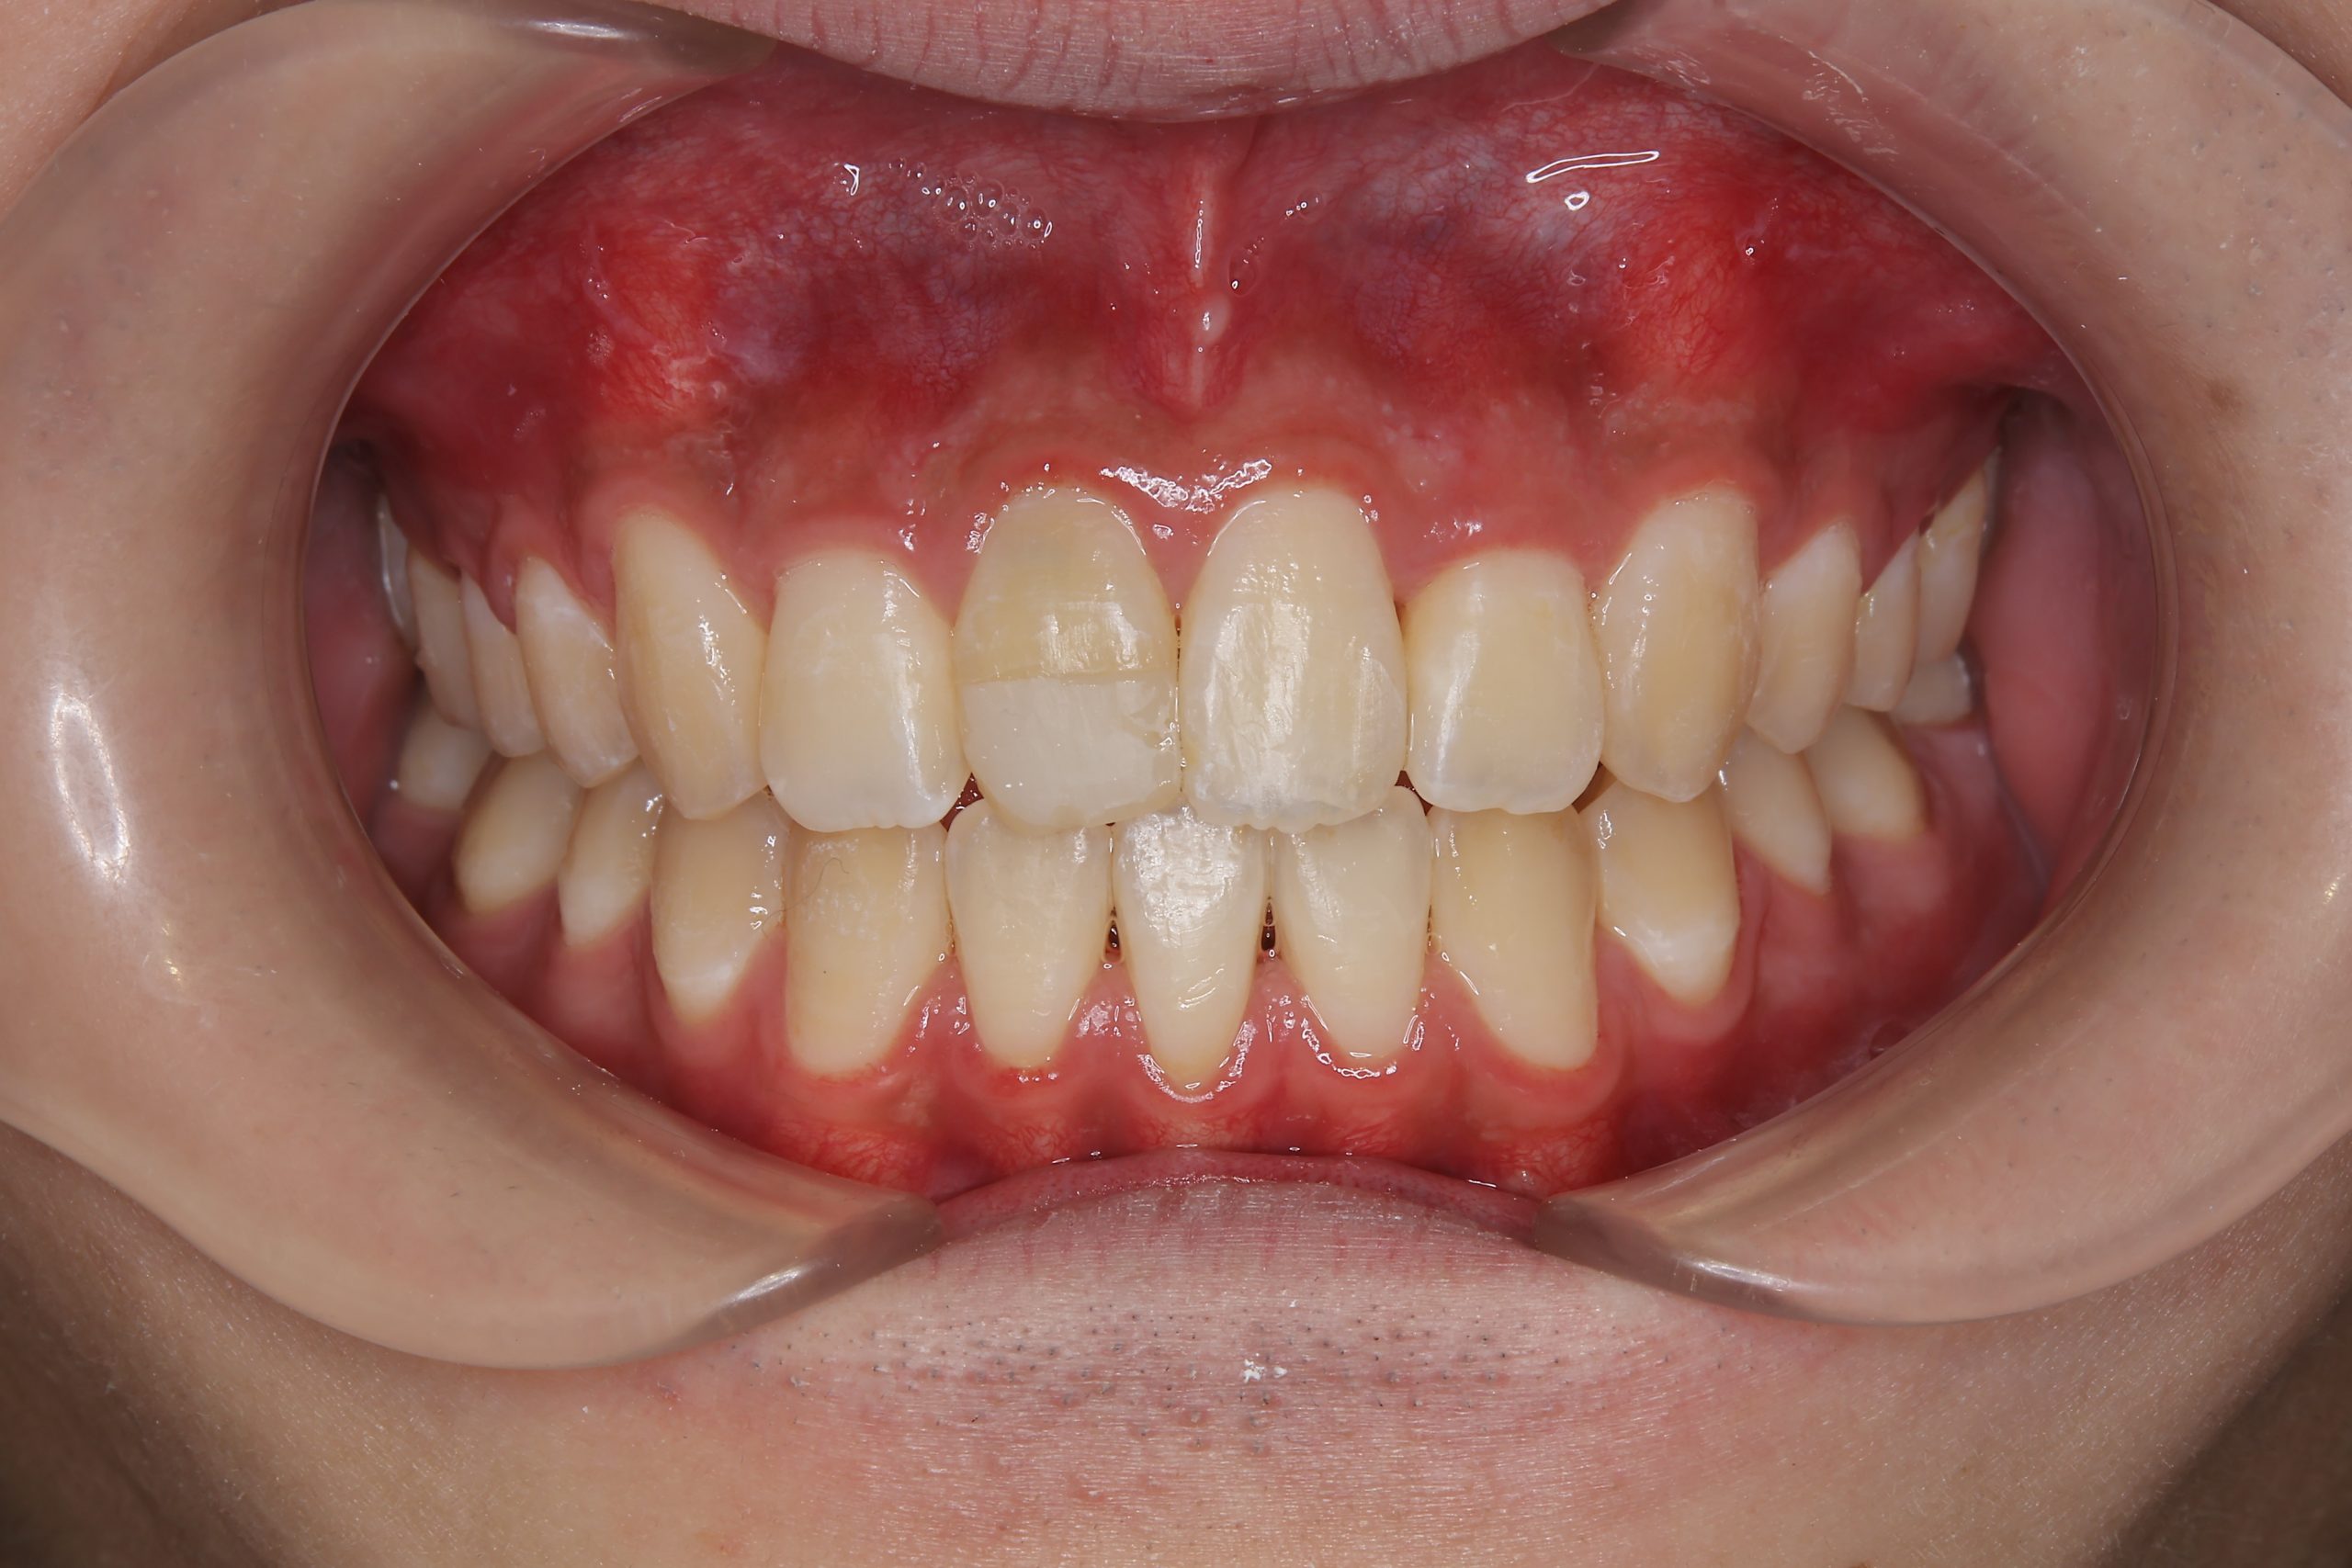

ビフォー

主訴 前歯が少し前に出ている|鼻づまり

施術内容 MSEと下顎リンガルアーチを用いて上下顎骨を拡大した。

その後をマルチブラケット装置を用いて非抜歯で歯牙を配列し、良好な咬合を獲得した。

治癒期間 1年6か月間